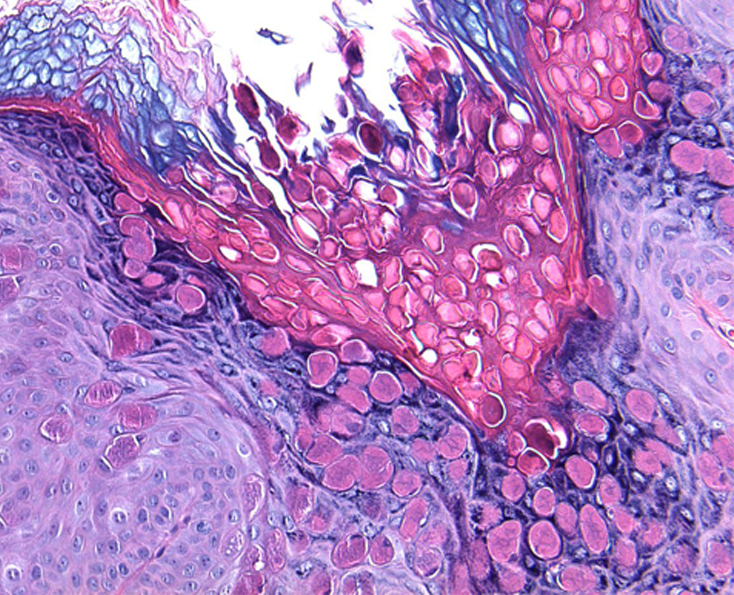

Клинические проявления неинфекционных заболеваний кожи при поражении аногенитальной области в целом не отличаются от таковых другой локализации. Однако целый ряд особенностей пораженной области – разная степень кератинизации эпителия, хорошая васкуляризация, окклюзия и мацерация кожным салом, потом и вагинальным отделяемым, высокий рH кожи (результат расщепления бактериальными уреазами мочевой кислоты с образованием аммиака), трение – нередко приводят к изменениям их клинической картины. Это существенно затрудняет распознавание заболеваний гениталий и перианальной области. Значительное сходство субъективной симптоматики и клинических проявлений дерматозы аногенитальной области имеют с инфекционными, а также предраковыми заболеваниями данной локализации, что нередко является одной из причин поздней диагностики дерматозов и предраков. Ситуация усложняется различием классификаций и терминов, используемых разными клиницистами

(акушерами-гинекологами, урологами, дерматологами) и морфологами, что приводит к непониманию и затрудняет преемственность (комплексный подход) в ведении этих пациентов

Лечение дерматозов аногенитальной локализации нередко представляет сложную задачу и требует междисциплинарного подхода. Основные подходы к лечению дерматозов данной локализации включают восстановление кожного барьера, назначение противовоспалительных препаратов, в частности топических глюкокортикостероидов и/или топических ингибиторов кальциневрина, реже – системных глюкокортикостероидов, ретиноидов, гидроксихлорохина или дапсона, ослабление субъективной симптоматики, профилактику и лечение вторичной инфекции. Отсутствие эффекта от противовоспалительной терапии требует исключения предраковых заболеваний вульвы и является показанием для диагностической биопсии.